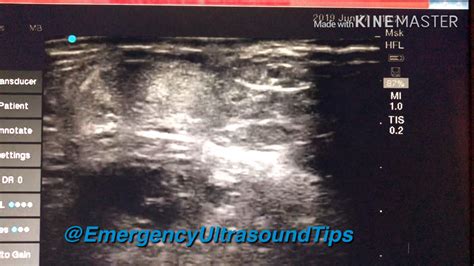

Ultrasound Scans Identify Partially Ruptured Achilles Symptoms Faster Now

Ruptured Achilles X Ray at Latanya Boring blog